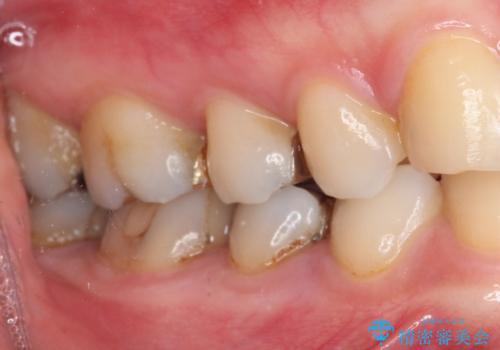

下の奥歯の虫歯をゴールドインレーで治療

ゴールドインレーは適合がよいため、虫歯の再発のリスクが少ない非常に優れた材料です。

ゴールドインレーはセラミックインレーと比べ、割れるリスクが低いため、咬合力が強い方にお勧めです。